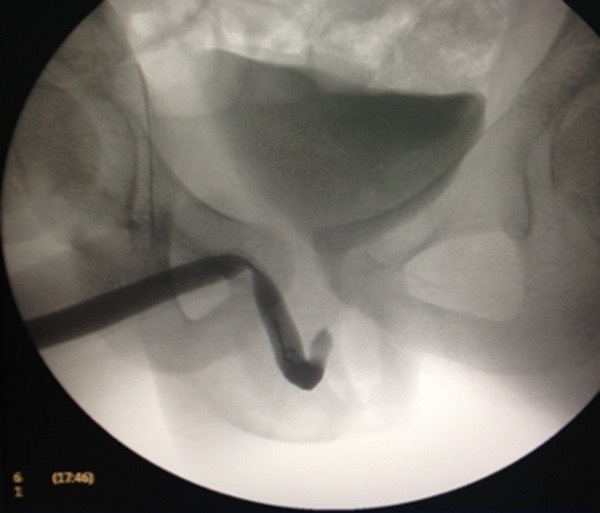

Уретрография под контролем рентгеноскопии показало отсутсвие признаков какой-либо экстравазации контраста,

Figure 2. Восходящее изображение уретрографии под контролем рентгеноскопии показывает отсутсвие признаков какой-либо экстравазации контраста.